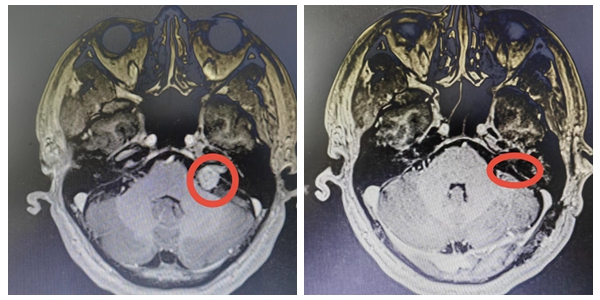

手术前后对比图

经过周密的术前准备,4月中旬,袁贤瑞教授带领姜尚军副主任医生、詹文亮主治医师等团队成员为曹先生进行了手术。术中见肿瘤位于左侧桥小脑角,约2*1.5*1.8cm大小,部分肿瘤伸入内听道,在电生理监测下为曹先生成功的全切了肿瘤,且三叉神经、面神经、蜗神经、后组颅神经及岩静脉保留完好。